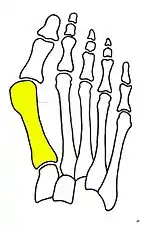

Normal foot skeleton

Fig 1a: Normal foot skeleton